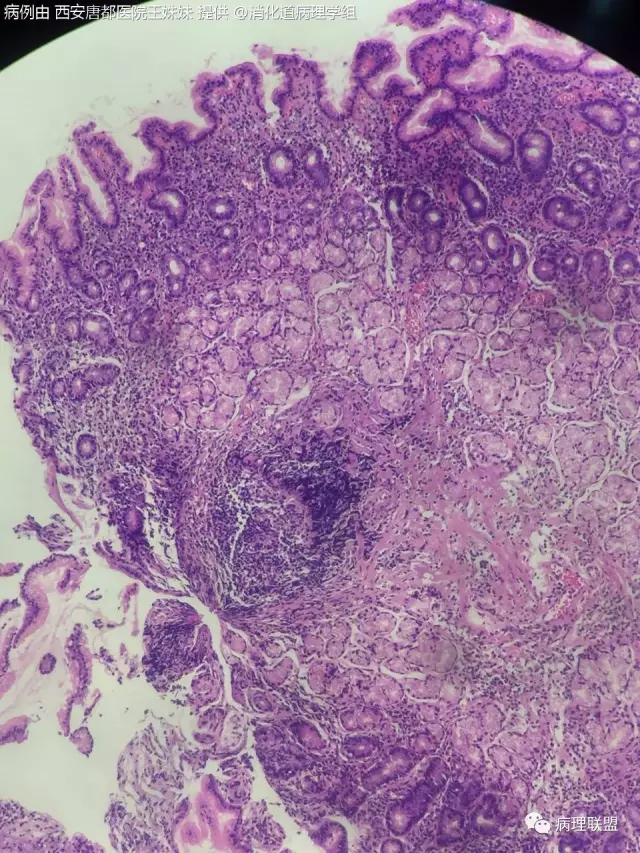

十岁的小孩可以报萎缩性胃炎么,各位老师,的确有腺体减少 淋巴滤泡形成。(病例由 西安唐都医院王姝妹 提供,致谢!)

有淋巴滤泡在下面,不能报萎缩。仔细观察,是否有HP感染,如果没有HP感染,建议加做 Syn CgA gastrin,观察是否存在神经内分泌细胞增生,排除自身免疫性胃炎